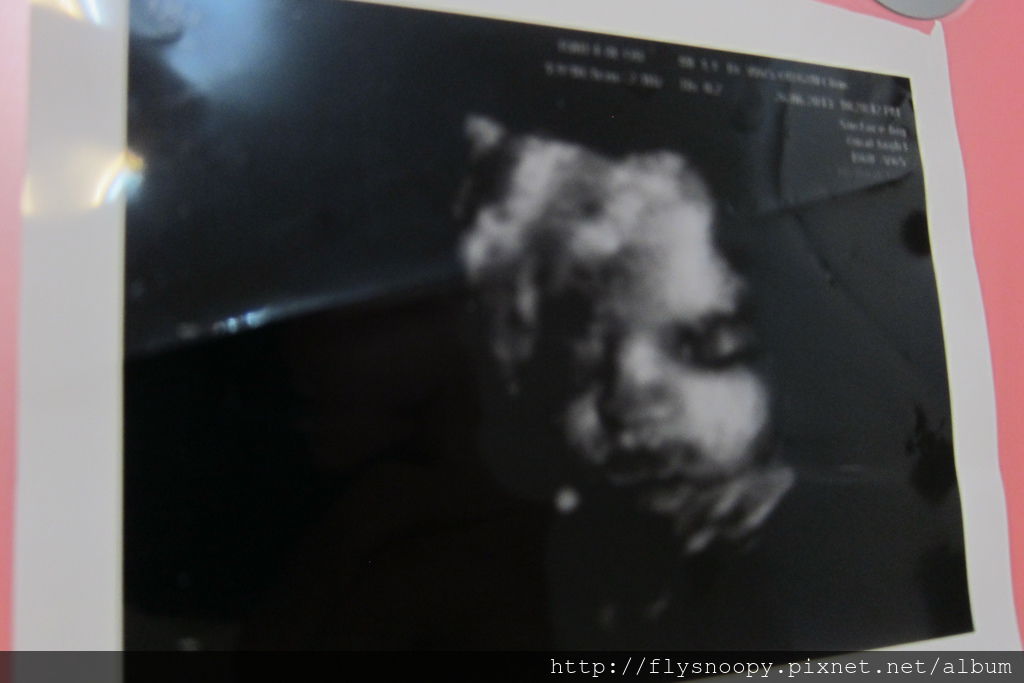

這次的4D照得好清楚,也比較可愛,

醫生說像我,但是我和老公都看不出來